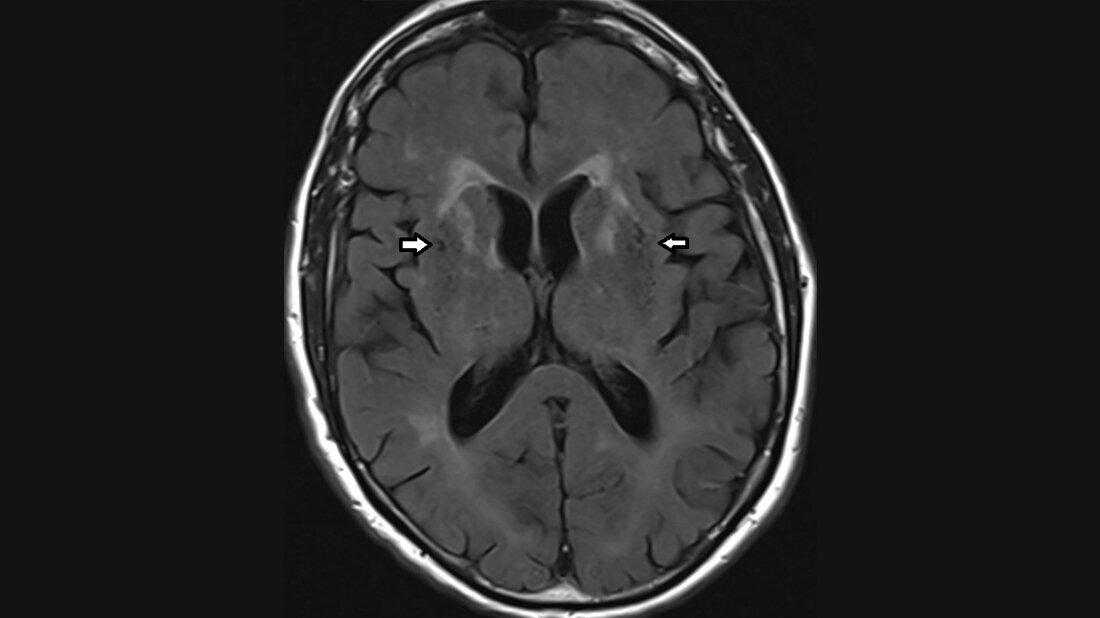

Die Virchow-Robin-Räume (VRR) sind die Erweiterung des Subarachnoidalraums, die die penetrierenden Arterien auf dem Weg zu den Basalganglien oder der grauen Substanz der Großhirnkonvexität umgeben. Kleine VRR werden in jedem Alter gefunden. Mit zunehmendem Alter nehmen die Anzahl und Größe zu. Die perivaskulären Räume wurden vor etwa 150 Jahren identifiziert.

Perivascular spaces (PVS) or Virchow-Robin’s spaces are piallined extensions of the subarachnoidal space that surround penetrating arteries as they enter either the basal ganglia or the cortical gray matter over the high convexities. Small PVS are found in patients of all ages. They increase in size and frequency with advanting age. Perivascular spaces were first identified over 150 years ago.